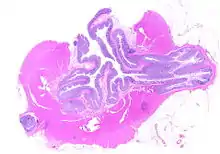

Diverticulosis is the condition of having multiple pouches (diverticula) in the colon that are not inflamed. These are outpockets of the colonic mucosa and submucosa through weaknesses of muscle layers in the colon wall,[1] and may be due in part to low-fiber diet prompting changes in intestinal microflora with consequent low-grade inflammation.[2] Diverticula don't cause symptoms in most people.[3] Diverticular disease occurs when diverticula become clinically inflamed, a condition known as diverticulitis.[4]

Pathophysiology

The precise mechanisms by which diverticula are formed are unknown.[1] Multiple theories have been proposed including genetic susceptibility, diet, intestinal motility, changes in the microbiome, and inflammation. One leading theory suggests that diverticula form in weakened areas of the colon wall that are subjected to increased pressure.[1] The strength of the colon wall is known to decrease with age.[1] Previous theories proposed that impacted fecal matter and certain foods would get stuck in diverticula (thereby causing trauma), which caused poor blood flow, death of the affected intestinal wall cells, and intestinal perforation.[1] Newer theories have called this paradigm into question.[1]